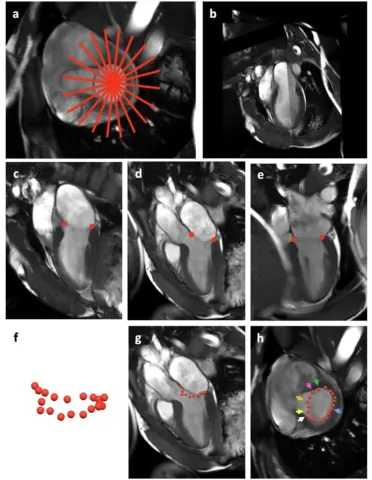

An axis-specific mitral annuloplasty ring eliminates mitral regurgitation allowing mitral annular motion in an ovine model

Zhu Y, Imbrie-Moore AM, Park MH, Cork TE, Yajima S, Wilkerson RJ, Tran NA, Marin-Cuartas M, Mullis DM, Baker SW, Tada Y, Ueyama T, Leipzig M, Wang VY, Ethiraj S, Madira S, Anilkumar S, Walsh SK, Lucian HJ, Huynh C, Morris K, Kim OS, Mulligan J, Wang H, Shudo Y, Ennis DB, Woo YJ. An axis-specific mitral annuloplasty ring eliminates mitral regurgitation allowing mitral annular motion in an ovine model. Commun Med (Lond). 2025 Feb 12;5(1):40. doi: 10.1038/s43856-025-00753-6. PMID: 39939395; PMCID: PMC11822063.